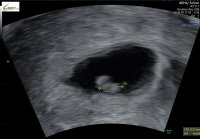

må vel også være noen unntak for å bekrefte regelenEn liten oppdatering på denne som altså skulle være gutt i følge denne metoden (og alle andre metoder jeg har lest om, kinesisk fødekart osv..). Det viste seg å være jentemå vel også være noen unntak for å bekrefte regelen

Bekreftet med nipt? Forøvrig så tar noen gynekologer undersøkelsen opp-ned og da blir det jo feil x)

Tror denne metoden blir vanskelig med mindre man vet sikkert hvilken side.

Bekreftet med NIPT, jajeg aner ikke hvordan bildet ble tatt, så kan godt være det er grunnen til at det ble «feil» også

Kort fortalt er det gjort en stor studie på 5000 tidlig ultralyder om at jentefoster fester seg på venstre side (morkake på venstre side) og omvendt for guttefoster (når man tar vaginal ultralyd.. om man tar utvendig ultralyd er sidene byttet om såklart) skal visst være 97 % sikkert. Prøv å Google det![]()